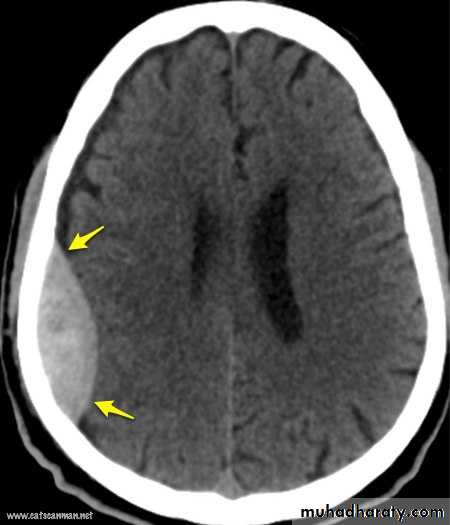

Trauma to the temporal region

The bone of calvarium is thinnest in the temporal fossa. Strong blows to the side head may cause a depressed fracture, in which a fragment of bone is depressed inward to compress or injure the brain. At the pterion , the middle meningeal artery is easily ruptured following such an injury CAUSING EXTRA DURAL HEMATOMA that compress the brain and could be fatal if untreated.28